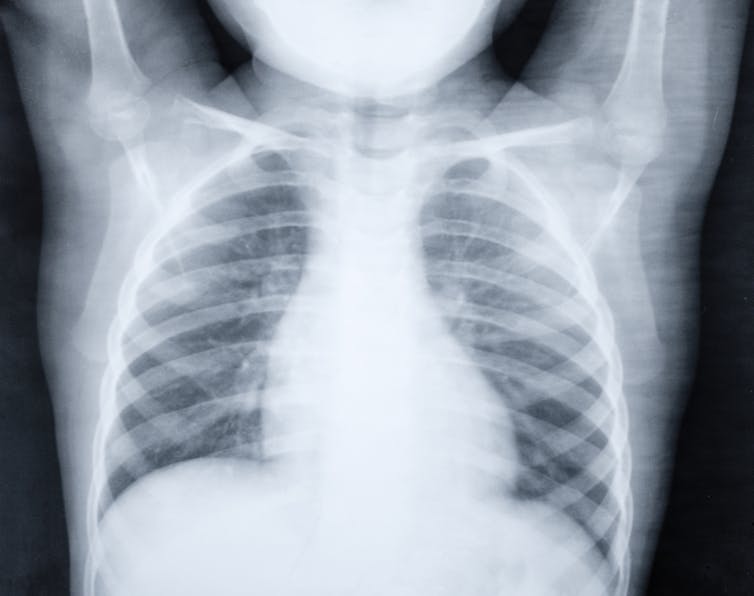

Pneumonia is a respiratory infection that affects the lungs. The viruses and bacteria that cause the disease are spread through airborne droplets from a cough or sneeze. An infection can cause the lungs to fill with pus and fluid, making breathing and oxygen intake difficult. And while anyone can get pneumonia, children with weakened immune systems or underlying illnesses are more susceptible. That’s why pneumonia kills more than a million children every year across the world.

Other advances are being made to improve pneumonia diagnosis. These include improved radiological methods, point-of-care tests which are used at or near patient care to speed up diagnosis, and the use of host biomarkers that examine the type of immune response a person develops to identify the cause of infection.